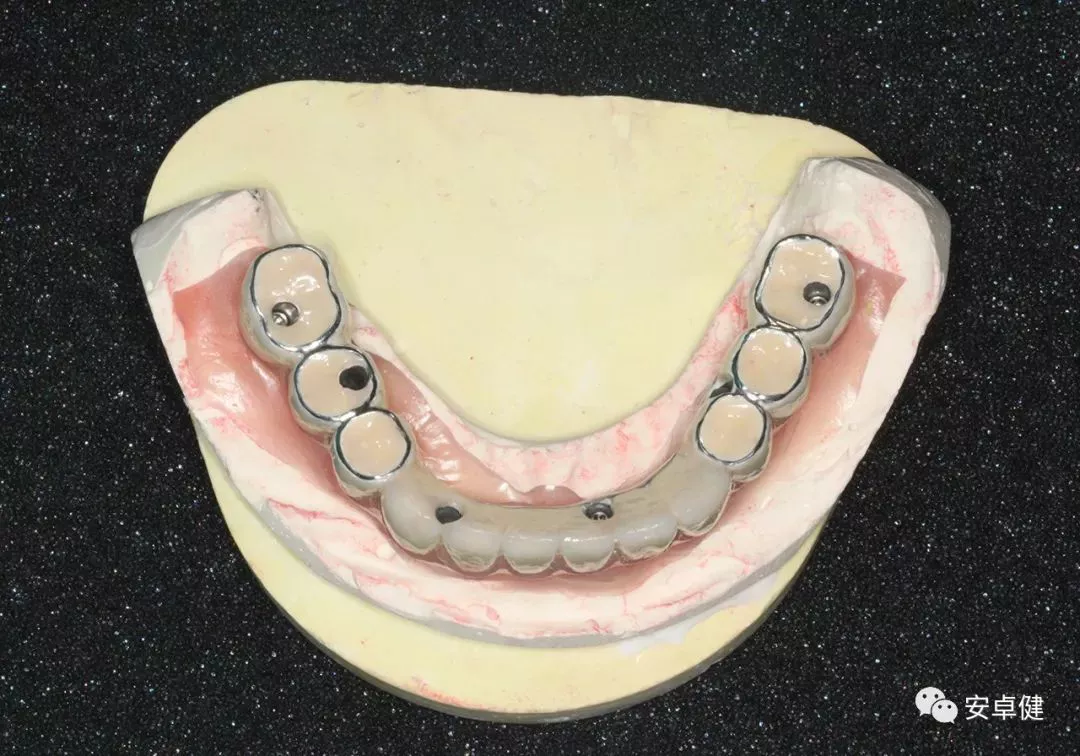

▷ 技工室制作

• 术后即刻制取印模后灌注石膏模型;

制作石膏模型

• 蜡型排牙于架就位,检查咬合及外形;

模型上架

即刻覆盖义齿蜡型上架

制作即刻覆盖义齿蜡型a.

制作即刻覆盖义齿蜡型b.

制作即刻覆盖义齿蜡型c.

• 制作即刻义齿,并上架检查其咬合关系及修复外形。

即刻覆盖义齿上架

▷ 最终修复体制作

最终修复体蜡型合面照

• 制作最终修复体蜡型,分别于架及口内试戴检查其外形及咬合;

• 完成最终修复体制作。

最终修复体合面照